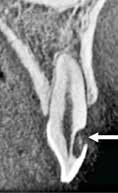

Fig. 1. A. Udsnit af panoramaoptagelse viser Ca(OH)2 uden for foramen apicale i en overkæbemolar og i sinus maxillaris (pil). B. Periapikal optagelse viser Ca(OH)2 uden for foramen apicale (pil) i en central incisiv. Tilfældet krævede kirurgisk indgreb.

Fig. 1 A. An orthopantomography section showing Ca(OH)2 beyond the apical foramen of maxillary first into the maxillary sinus (arrow) and (B) a periapical radiograph with Ca(OH)2 extrusion beyond the apical foramen (arrow) of a central incisor which required surgical intervention.

Ved mistanke om malpraksis vurderer man behandlerens handlinger i alle stadier i relation til opgavens kompleksitet og tager stilling til, om disse lever op til normen for almindelig anerkendt faglig standard. De mest omfattende skadevirkninger ses i forbindelse med anvendelse af endodontiske skyllevæsker og andre medikamenter, fx ulykker med natriumhypoklorit eller skader på nervevæv eller i sinus som følge af udpresning af calciumhydroxid igennem foramen apicale (Fig. 1A og B) (5,6). Sådanne uheld vurderes ofte til at være undgåelige, idet tandlægen ikke har levet op til normal faglig standard. Frygt for at begå procedurefejl eller andre utilsigtede hændelser bør dog ikke få klinikeren til helt at afstå fra at foretage endodontiske behandlinger (7).